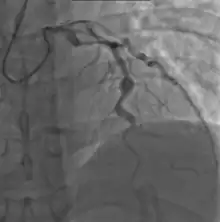

- Angiography was historically used to detect coronary artery aneurysms, and remains the gold standard for their detection, but is rarely used today unless coronary artery aneurysms have already been detected by echocardiography.

Heart complications are the most important aspect of Kawasaki disease, which is the leading cause of heart disease acquired in childhood in the United States and Japan.[31] In developed nations, it appears to have replaced acute rheumatic fever as the most common cause of acquired heart disease in children.[15] Coronary artery aneurysms occur as a sequela of the vasculitis in 20–25% of untreated children.[52] It is first detected at a mean of 10 days of illness and the peak frequency of coronary artery dilation or aneurysms occurs within four weeks of onset.[48] Aneurysms are classified into small (internal diameter of vessel wall <5 mm), medium (diameter ranging from 5–8 mm), and giant (diameter > 8 mm).[31] Saccular and fusiform aneurysms usually develop between 18 and 25 days after the onset of illness.[15]

Laboratory evidence of increased inflammation combined with demographic features (male sex, age less than six months or greater than eight years) and incomplete response to IVIG therapy create a profile of a high-risk patient with Kawasaki disease.[58][152] The likelihood that an aneurysm will resolve appears to be determined in large measure by its initial size, in which the smaller aneurysms have a greater likelihood of regression.[153][154] Other factors are positively associated with the regression of aneurysms, including being younger than a year old at the onset of Kawasaki disease, fusiform rather than saccular aneurysm morphology, and an aneurysm location in a distal coronary segment.[60] The highest rate of progression to stenosis occurs among those who develop large aneurysms.[4] The worst prognosis occurs in children with giant aneurysms.[155] This severe outcome may require further treatment such as percutaneous transluminal angioplasty,[156] coronary artery stenting,[157] bypass grafting,[158] and even cardiac transplantation.[159]